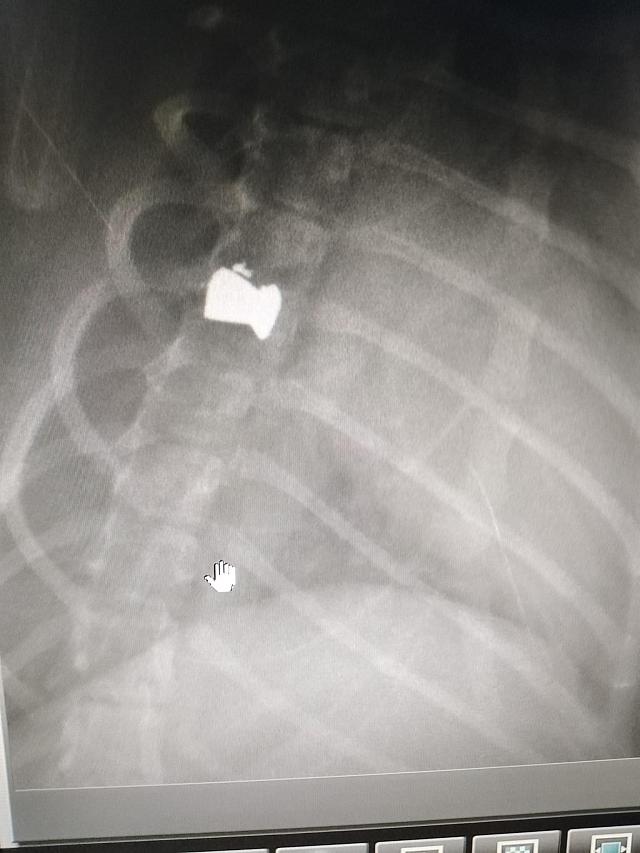

Ο 5μηνών Bullet έχει μια σφαίρα καρφωμένη στην σπονδυλική στήλη ( σπόνδυλος Θ8) που του έχει παραλύσει τα πίσω πόδια και του έχει δημιουργήσει πρόβλημα στο ουρολογικό του .

ακτινογραφια